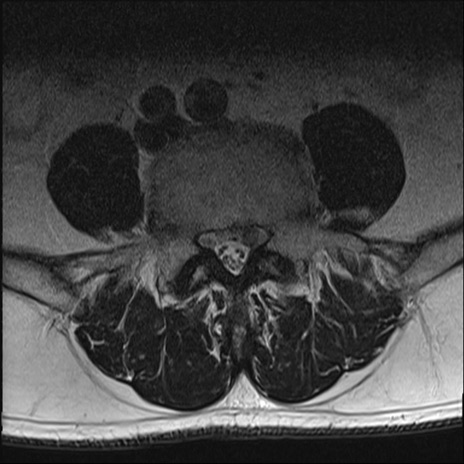

【整形】TIPS症例2 腰椎MRI T2WI(横断像)

【症例】70歳代男性

【主訴】左下肢痛

【現病歴】2週間前くらいから腰痛、左下肢痛あり。左臀部から大腿、下腿外側のしびれが常時ある。歩行とともに同部位の痛みあり。

【身体所見】Lasegue70-/60+、Bragard-/±、PTR ±/±、ATR -/-、IP 5/5、TA 5/4、TS 5/5、EHL 右第1足趾なし/3、FHL 5/5、hypersthesia(-)、足背動脈触知良好

異常所見と診断は?